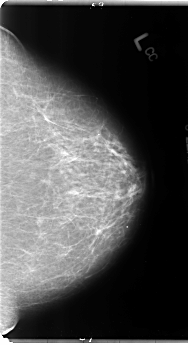

B_3106_1.RIGHT_CC

LEFT_CC LINES 4824 PIXELS_PER_LINE 2624 BITS_PER_PIXEL 12 RESOLUTION 50 NON_OVERLAY